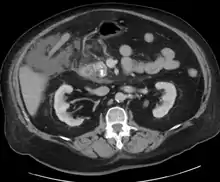

For imaging, abdominal ultrasound is convenient, simple, non-invasive, and inexpensive.[32] It is more sensitive and specific for pancreatitis from gallstones than other imaging modalities.[30] However, in 25–35% of patients the view of the pancreas can be obstructed by bowel gas making it difficult to evaluate.[29]

A contrast-enhanced CT scan is usually performed more than 48 hours after the onset of pain to evaluate for pancreatic necrosis and extrapancreatic fluid as well as predict the severity of the disease. CT scanning earlier can be falsely reassuring.

ERCP or an endoscopic ultrasound can also be used if a biliary cause for pancreatitis is suspected.